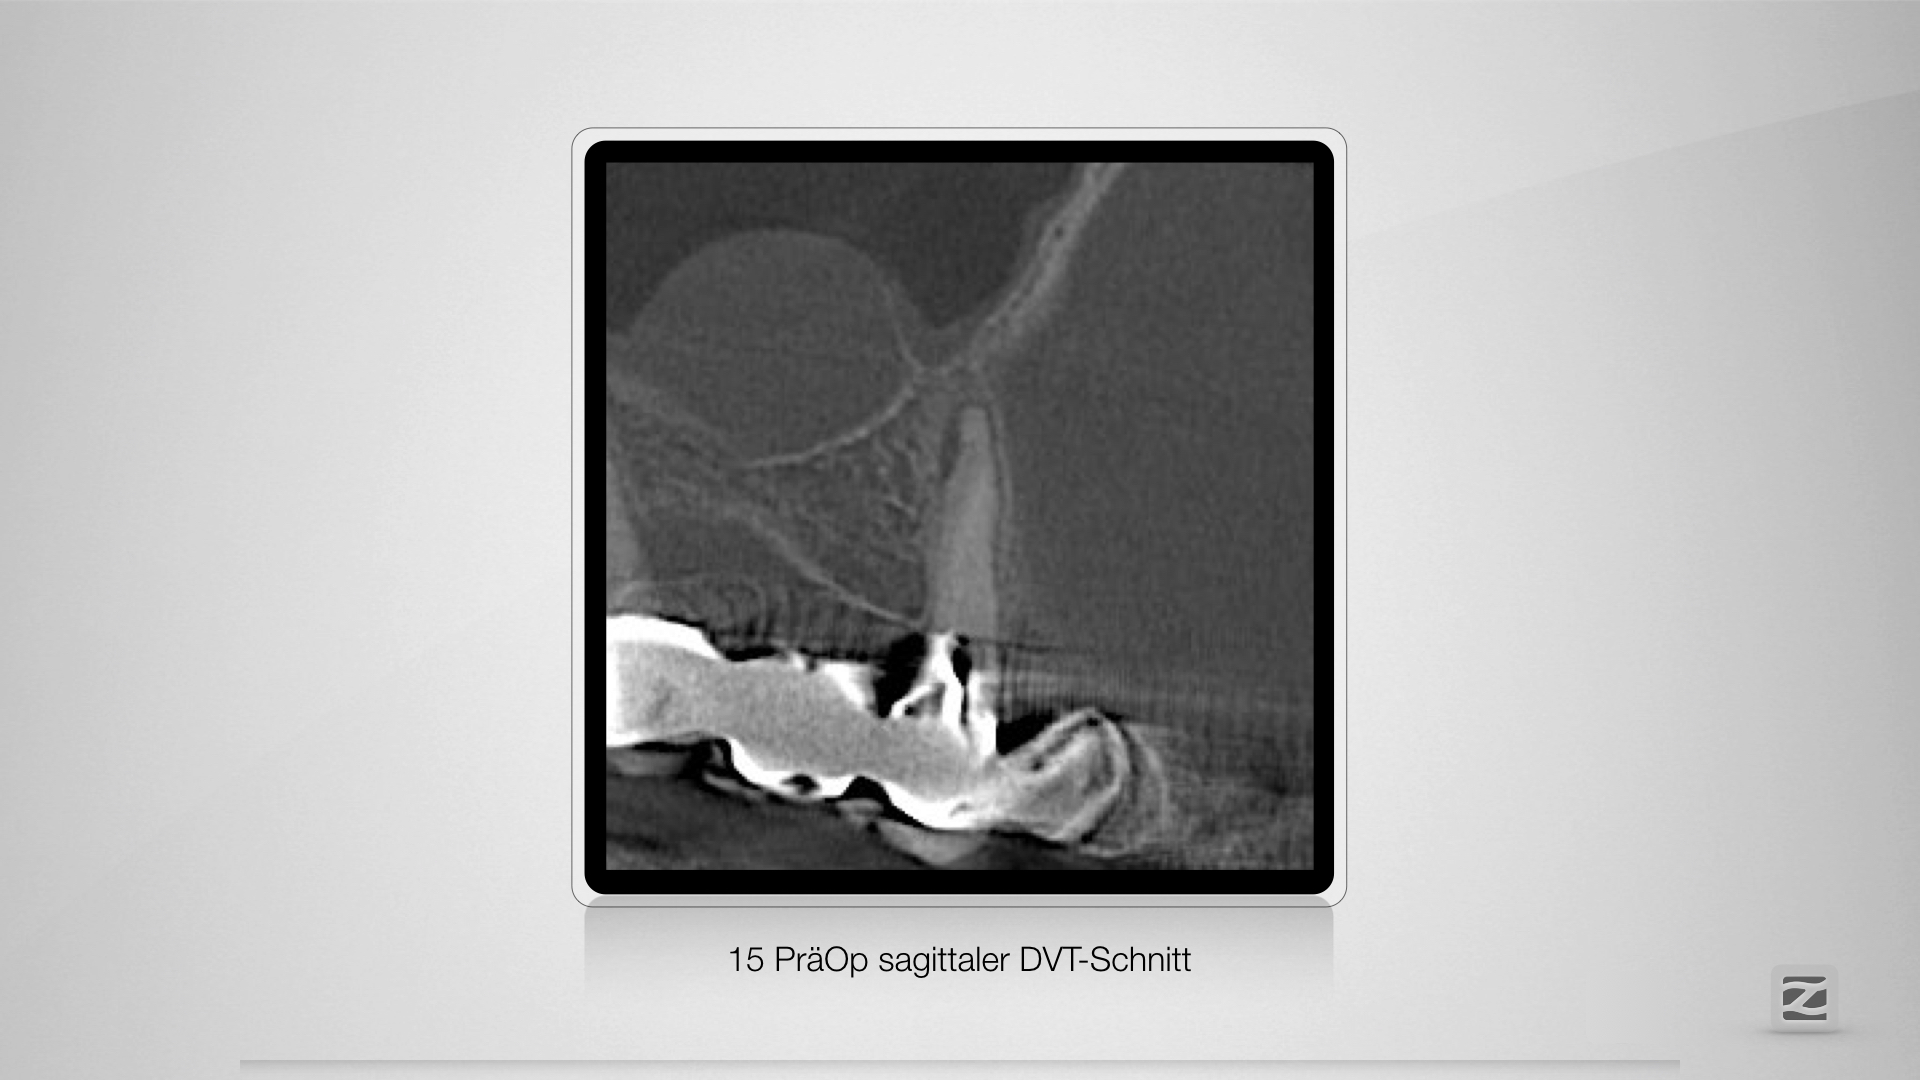

Herausgeschält